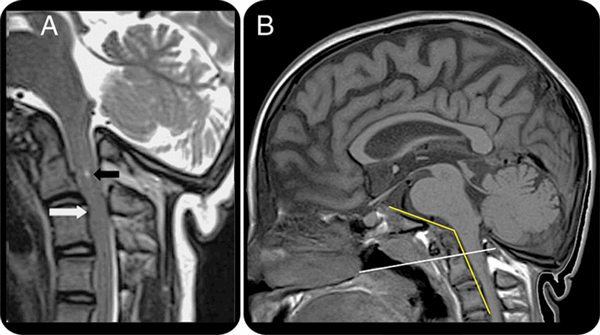

(Слева) На схеме в сагиттальной проекции показан пример фатальной атланто-затылочной диссоциации с полным перерывом спинного мозга на уровне кранио-вертебрального сочленения. Кроме перерыва может наблюдаться и тракционное повреждение спинного мозга с развитием неврологического дефицита.

(Справа) Рентгенограмма в боковой проекции: отделение мыщелка затылочной кости от С1. Отношение Пауэрса (> 1), БАИ (> 12 мм) и БДИ (> 12 мм) являются классическими рентгенологическими критериями диагностики атланто-затылочной диссоциации. (Слева) КТ, сагиттальный срез: увеличение БДИ. В норме этот интервал на КТ-срезах у взрослых не должен превышать 8,5 мм, а на рентгенограммах в боковой проекции - 12 мм.

(Справа) КТ, сагиттальный срез: в мягкотканном режиме в вентральной части эпидурального пространства определяется гиперденсный участок, соответствующий кровоизлиянию. Патологический мягкотканный компонент также виден в надзубовидной области, что соответствует кровоизлиянию в области расположенной здесь связки. Кадаверные исследования показали, что для того, чтобы произошла АЗД, необходимо наступление разрыва текториальной мембраны и крыловидных связок.

На МРТ краниовертебрального перехода − платибазия и базилярная импрессия при несовершенном остеогенезе